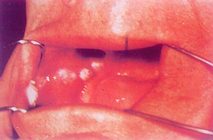

1.斑块状 口腔粘膜上出现白色或灰白色的均质型较硬的斑块,质地紧密,损害形态与面积不等,轻度隆起或高低不平。值得注意的是,损害大小同癌变的可能性之间并无平行关系,有时即使只有米粒大小时已发生癌变。斑块状损害的肉眼所见,往往很难同白念菌白斑相鉴别,但扪时前者较硬。(彩图1)

彩图1 白斑病